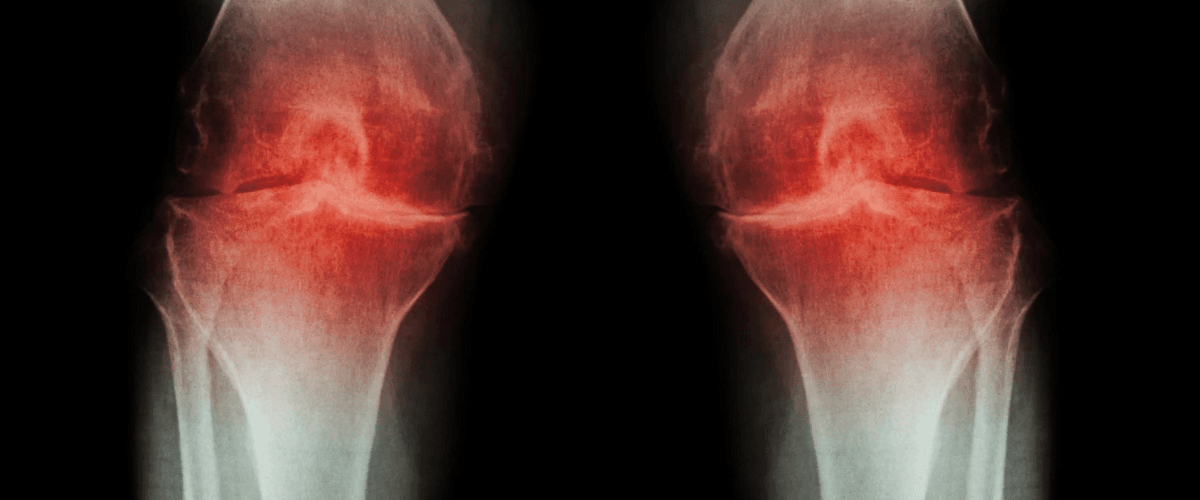

Суставной хрящ — мягкая амортизирующая ткань, выстилающая кости и на 75% состоящая из воды. Она снижает нагрузку на суставы, но с возрастом или в результате серьезных нагрузок хрящи разрушаются, возникают воспаления и боли, а затем развивается артрит и другие заболевания. В зрелом возрасте человек почти не способен восстановить поврежденный хрящ естественным образом, однако ученые из Университета Стэнфорда придумали, как вырастить суставной хрящ заново.

В итоге ученые получили суставные хрящи, механические свойства которых были сравнимы со свойствами натуральных хрящей. Больные остеоартритом мыши, на которых проводились опыты, восстановили подвижность и избавились от болей.

Тот же процесс оказался действенным и для мышей с человеческими тканями. Это значит, что операция по регенерации хрящей поможет и людям. Сначала исследователи планируют провести клинические испытания на суставах пальцев, а потом перейти к более крупным — локтям и коленям.